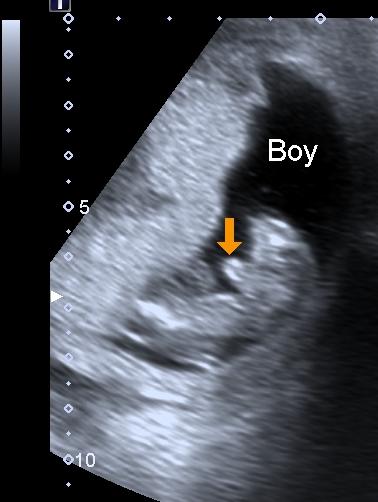

Yes, by performing an ultrasound scan at week 5 , your doctor or the technician will be able to tell whether you are carrying twins or not . Based on whether the twins are fraternal or identical, you will be able to see them .

Dating ultrasound : Due date confirmation . To determine your baby's gestational age, the sonographer will measure the crown-rump length, which generally indicates the baby's date of arrival . What will they be checking at the first ultrasound ? Heartbeat . At six weeks , sonographers may be able to see a heartbeat on the monitor (more on this below) .